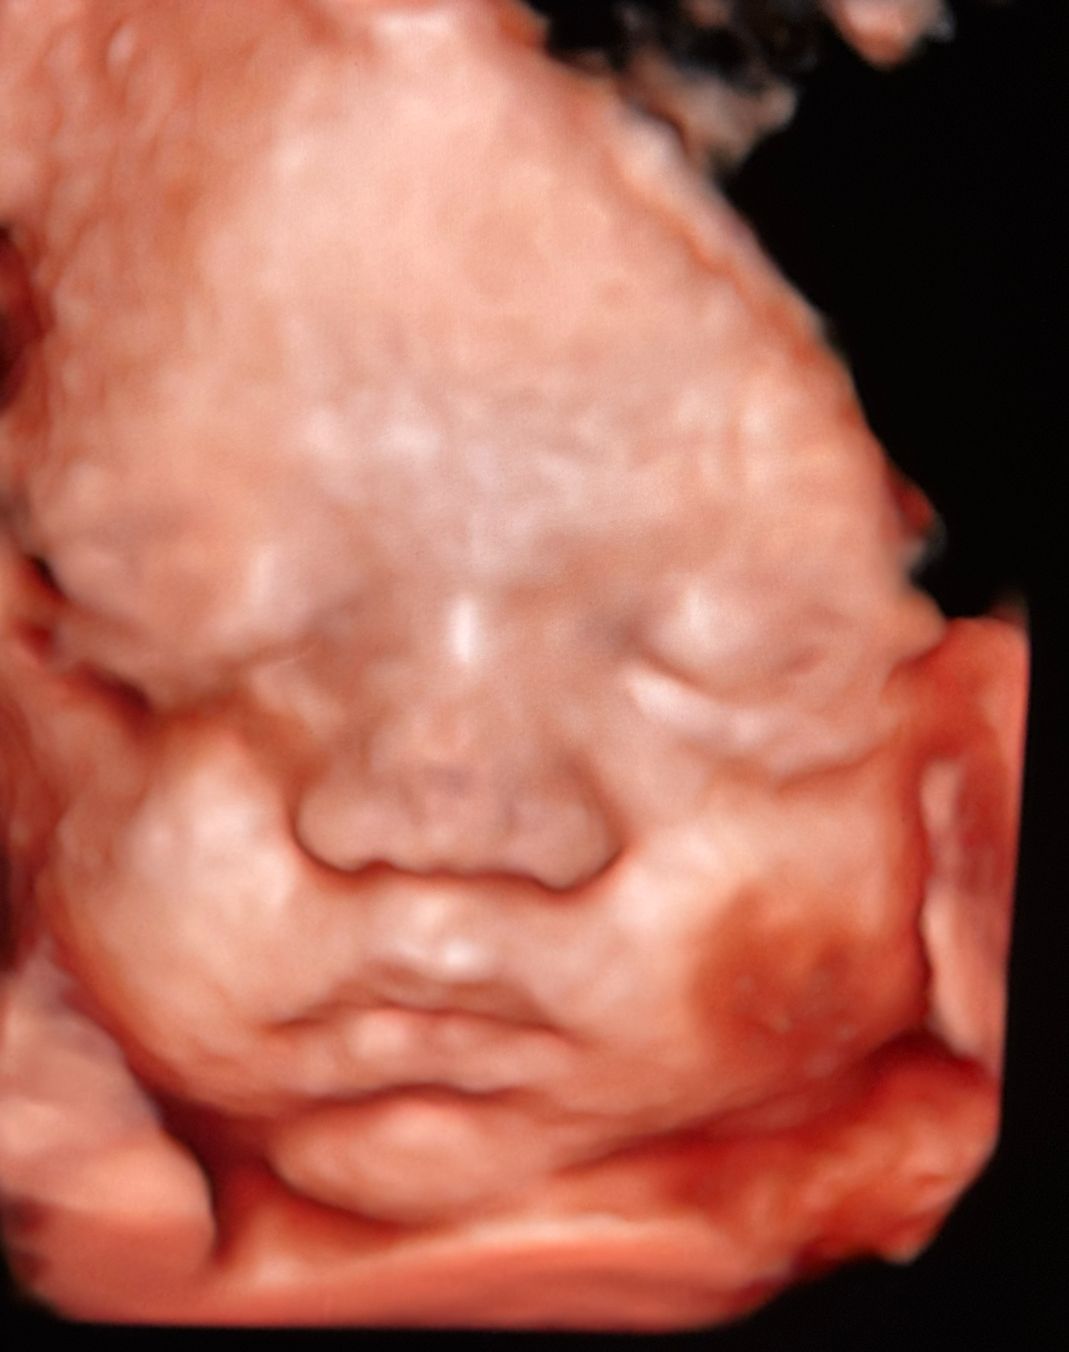

Mi occupo della gestione delle gravidanze fisiologiche e a rischio ed eseguo ecografie ostetriche in tutti i trimestri di gravidanza, tra cui ecografia di datazione, bitest e traslucenza nucale, ecografia morfologica, ecografia del III trimestre con flussimetria fetale, cervicometria ed ecografie 3D/4D, fondamentali per una corretta diagnosi e per il monitoraggio della salute materno-fetale.

ecografia ostetrica 3D/4D 215 €